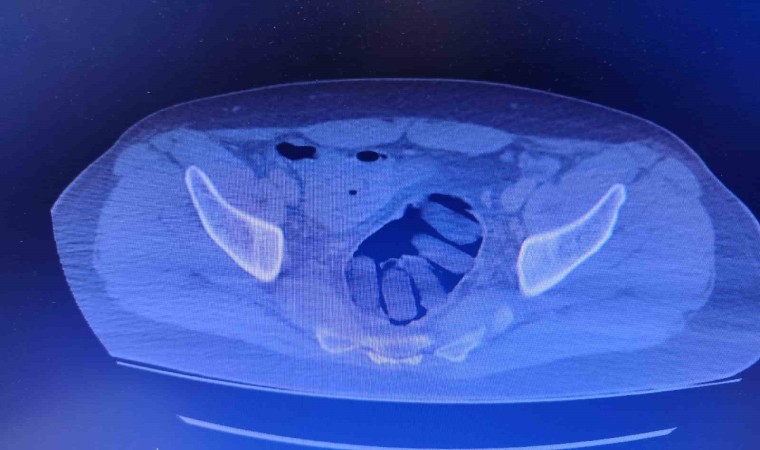

Kırşehir İl Emniyet Müdürlüğü Narkotik Suçlarla Mücadele Şube Müdürlüğü ekipleri tarafından yapılan çalışmalarda yabancı uyruklu Y.S. ve H.S.’nin doğu illerinden ülkeye kaçak yollarla girdikleri ve batı illerine uyuşturucu madde kuryeliği yaptıkları tespit edildi. Takibe alınan uyuşturucu kuryelerinin seyahat ettiği yolcu otobüsü Kırşehir’de durduruldu. Gözaltına alınan ve hastaneye götürülen şahısların midelerinde kapsül bulunduğu tespit edildi. Şahısların midelerinde zulaladığı 126 kapsül halinde 1 kilo 300 gram ve 44 kapsül halinde 550 gram uyuşturucu madde ele geçirildi.